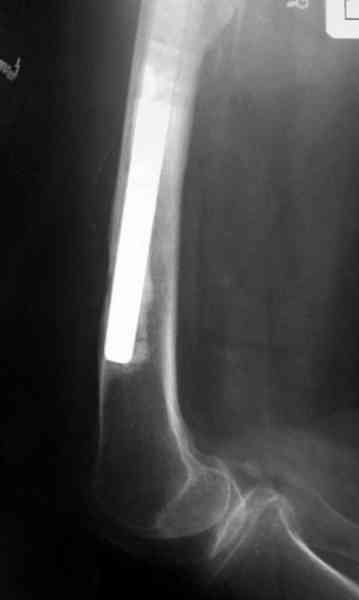

Представляю вашему вниманию снимки (прошу прошения за качество снимков) больной 48 лет с ревматоидным артритом, которой был сделан тотальный эндопротез справа,

контрольный снимок сделали только на 21день после операции (№1) и с интервалом 5 дней второй снимок (№2)

Судя по всему, произошел раскол наружной стенки бедра и ножка находится вне костного канала. В таком случае

решение одно - удаление ножки и установка новой в расчете на дистальную фиксацию. Конктреную модель подсказать тяжело из-за низкого качества Р-грамм.